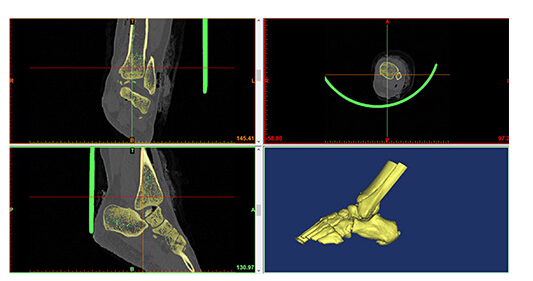

西安高新醫(yī)院骨科首席專(zhuān)家賀西京教授根據(jù)患者的病情結(jié)合目前國(guó)際先進(jìn)的3D打印技術(shù)為患者“私人定制”量身定做個(gè)體化距骨實(shí)施假體置入術(shù),手術(shù)由賀西京教授親自主刀,骨一科宋明輝主任、楊益宏副主任等配合完成,手術(shù)團(tuán)隊(duì)具有豐富的臨床經(jīng)驗(yàn)和高超的手術(shù)技術(shù),從而使踝部重要神經(jīng)血管和皮膚軟組織血運(yùn)得到良好的保護(hù);假體由國(guó)內(nèi)知名人工關(guān)節(jié)制造企業(yè)提供,保證假體的高性能、生物相容性及產(chǎn)品可操作性,手術(shù)過(guò)程制定嚴(yán)密的應(yīng)急處置方案,保證患者手術(shù)順利進(jìn)行。術(shù)前經(jīng)醫(yī)院倫理委員會(huì)論證及請(qǐng)示院領(lǐng)導(dǎo)、醫(yī)教部及相關(guān)部門(mén)決定實(shí)施手術(shù)。

該項(xiàng)新技術(shù)由于已在術(shù)前把患者的數(shù)據(jù)做了精確的測(cè)量,誤差小于0.01毫米,手術(shù)変得更加精準(zhǔn),創(chuàng)傷更小,出血更少,手術(shù)時(shí)間更短,有了3D打印技術(shù),很多并發(fā)難題迎刃而解,這就是高科技給我們帶來(lái)的希望。